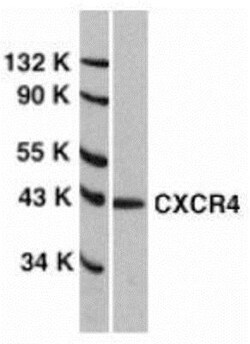

CXCR4 Polyclonal specifically detects CXCR4 in Human, Mouse, Rat samples. It is validated for Western Blot, ELISA, Immunohistochemistry, Immunocytochemistry/Immunofluorescence, Immunohistochemistry-Paraffin, Knockdown Validated.

| 40 kDa | |

| Western Blot | |

| Western Blot 1-2 μg/mL, ELISA 1:100-1:2000, Immunohistochemistry 5 μg/mL, Immunocytochemistry/Immunofluorescence 4 μg/mL, Immunohistochemistry-Paraffin 5 μg/mL, Knockdown Validated | |

| Human CXCR4 has four isoforms, including isoform a (356aa, 40.2kD), isoform b (352aa, 39.7kD), isoform c (423aa, 47.6kD), and isoform d (385aa, 43.4kD). This antibody detects human isoform b only, but not other human isoforms. Mouse CXCR4 has two isoforms, including isoform 1 (359aa, 40.4kD) and isoform 2 (357aa, 40.2kD). Rat CXCR4 has only one isoform identified so far (349aa, 39.4kD). | |